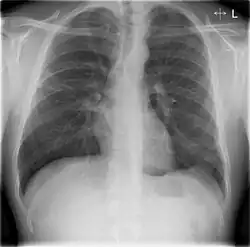

Chest X-rays of a CAP patient before (left) and after treatment

CAP is treated with an antibiotic that kills the infecting microorganism; treatment also aims at managing complications. If the causative microorganism is unidentified, which is often the case, the laboratory identifies the most effective antibiotic; this may take several days.

Chest X-rays and X-ray computed tomography (CT) can reveal areas of opacity (seen as white), indicating consolidation.[14] CAP does not always appear on x-rays, sometimes because the disease is in its initial stages or involves a part of the lung not clearly visible on x-ray. In some cases, chest CT can reveal pneumonia not seen on x-rays. However, congestive heart failure or other types of lung damage can mimic CAP on x-ray.[16]

Ceftriaxone and azithromycin are often used to treat community-acquired pneumonia, which usually presents with a few days of cough, fever, and shortness of breath. Chest x-ray typically reveals a lobar infiltrate (rather than diffuse).[20]